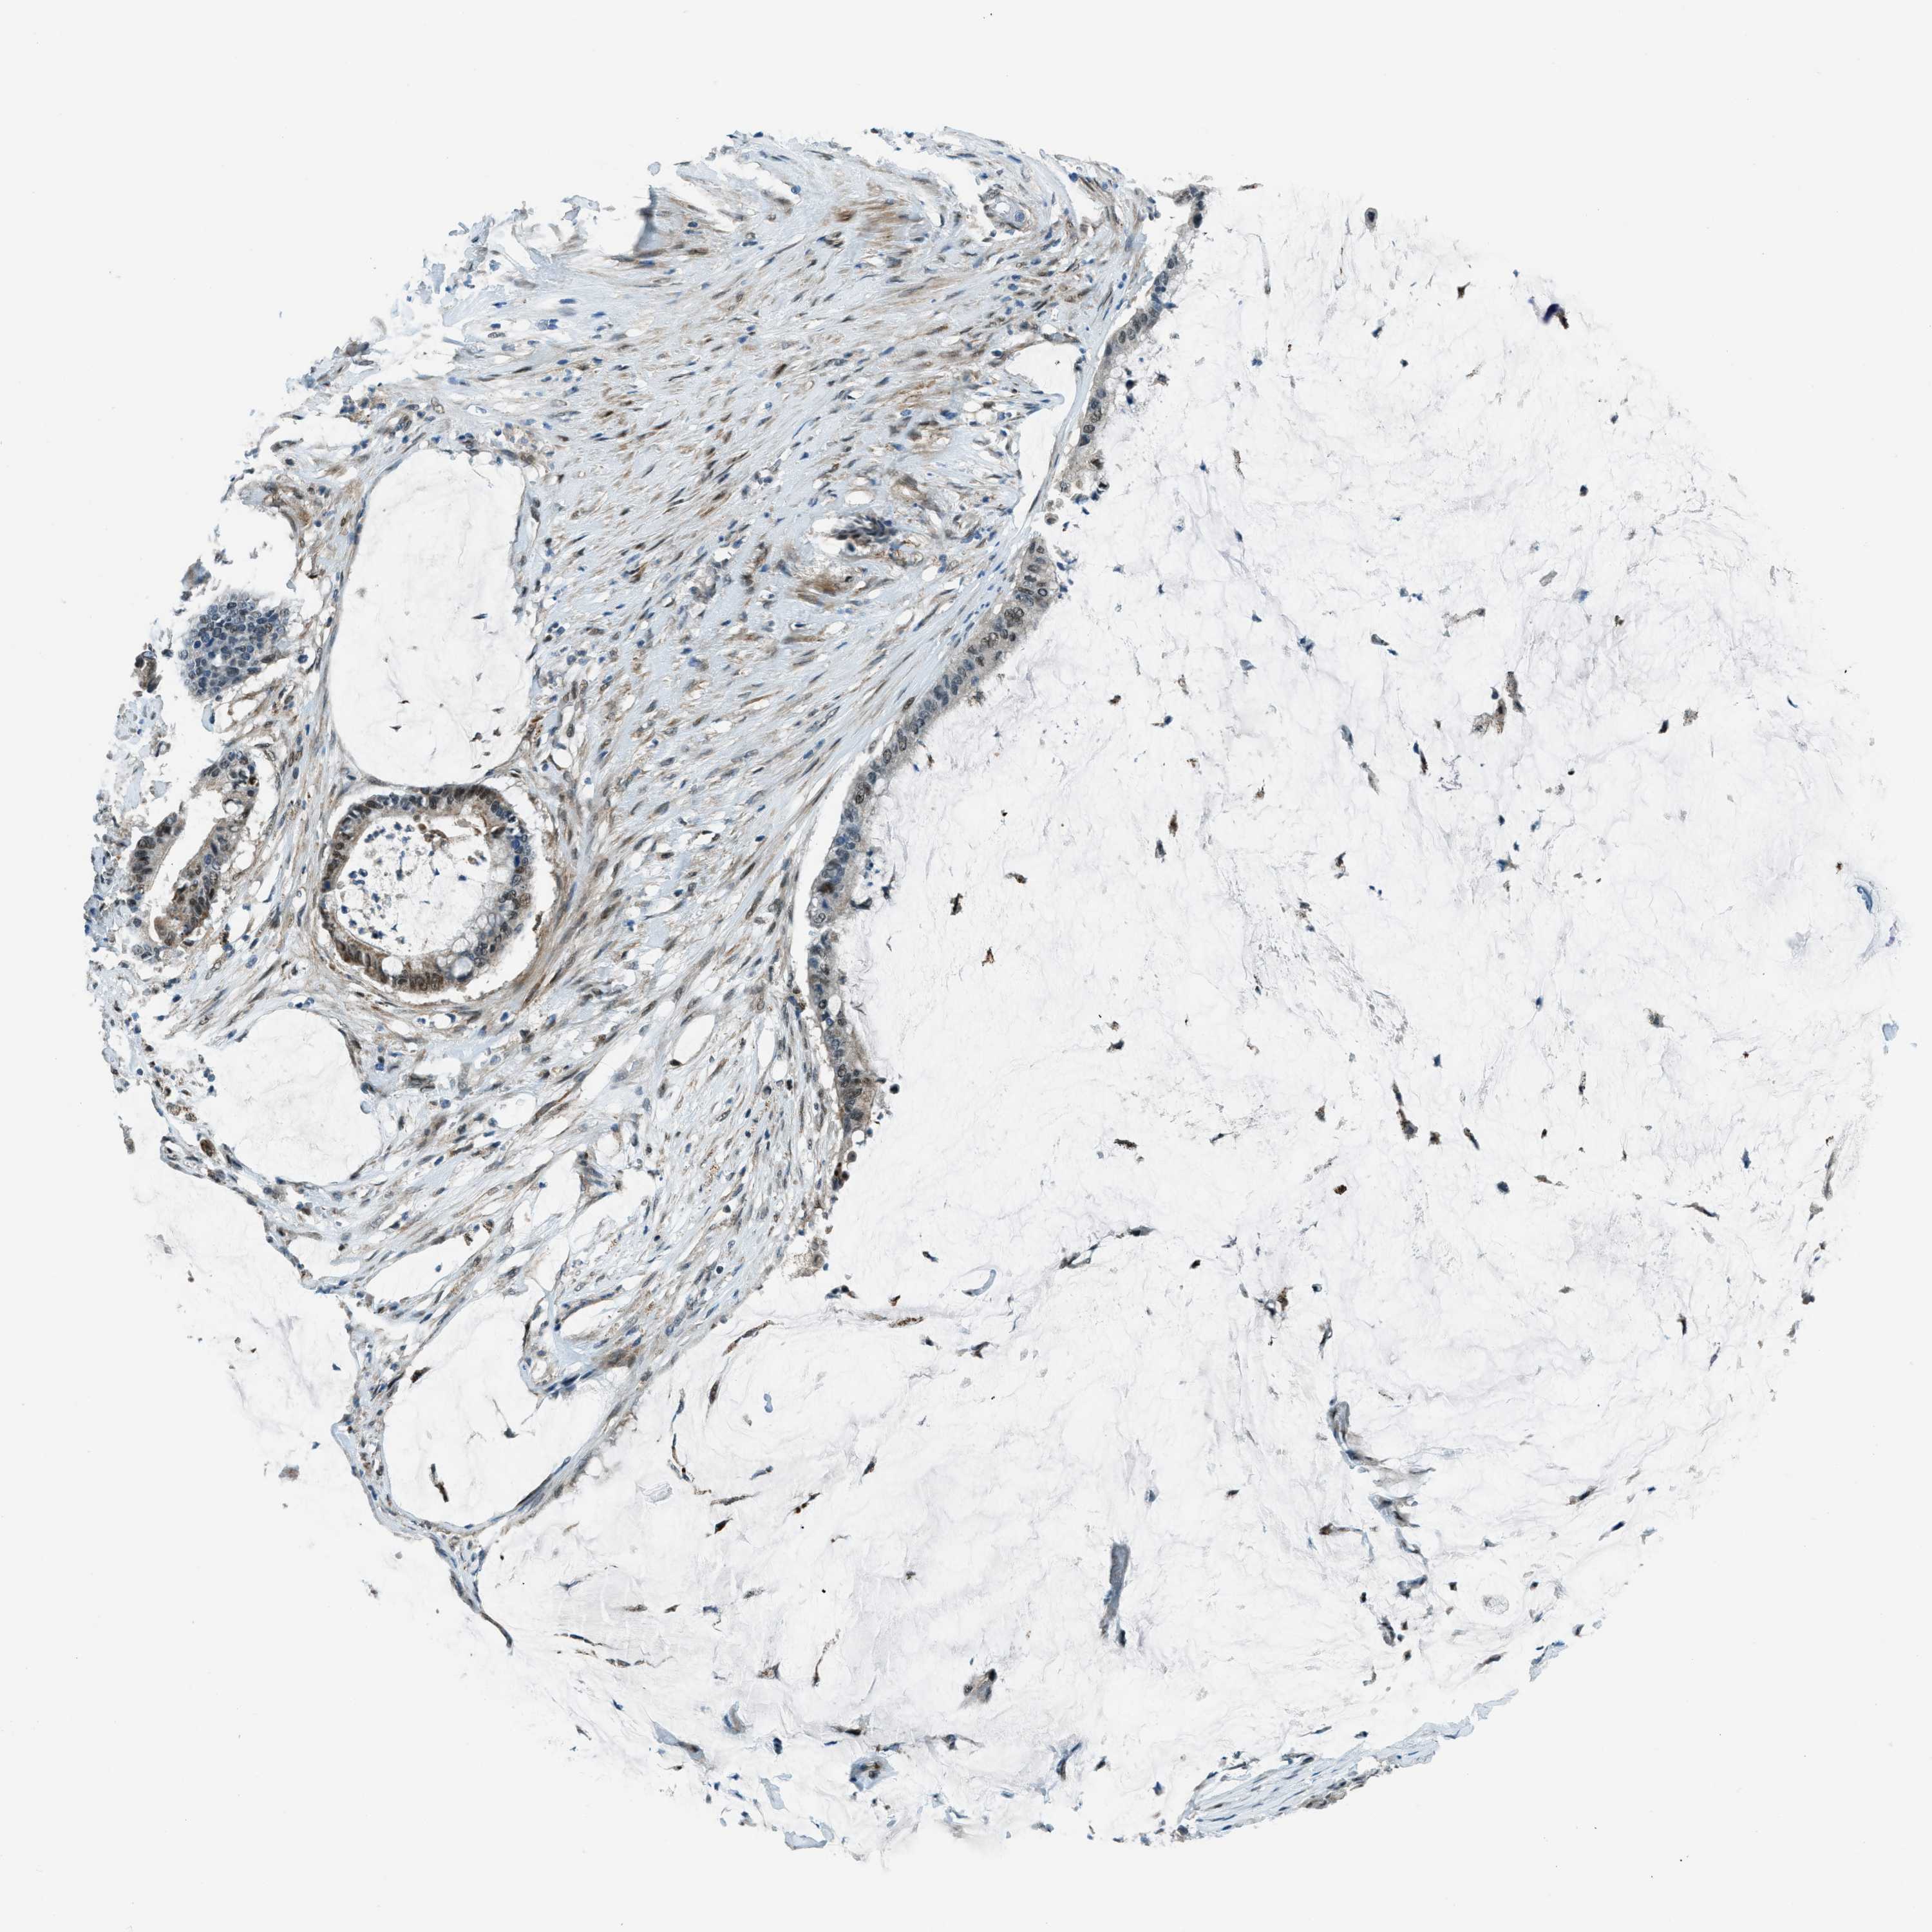

PANCREATIC CANCER - Protein expressioni

A mouse-over function shows sample information and annotation data. Click on an image to view it in a full screen mode. Samples can be filtered based on level of antibody staining by selecting one or several of the following categories: high, medium, low and not detected. The assay and annotation is described here.

Note that samples used for immunohistochemistry by the Human Protein Atlas do not correspond to samples in the TCGA dataset.

Antibody stainingi

Antibody staining in the annotated cell types in the current human tissue is reported as not detected, low, medium, or high, based on conventional immunohistochemistry profiling in selected tissues. This score is based on the combination of the staining intensity and fraction of stained cells.

Each image is clickable and will lead to virtual microscopy that enables deeper exploration of all samples and also displays staining intensity scores, fraction scores and subcellular localization as well as patient and tissue information for each sample.

Antibody HPA036356

Antibody CAB004986

Antibody CAB017025

Staining

High

Medium

Low

Not detected

Intensity

Strong

Moderate

Weak

Negative

Quantity

>75%

75%-25%

<25%

None

Location

Nuclear

Cytoplasmic/membranous

Cytoplasmic/membranous,nuclear

Adenocarcinoma, NOS

Adenocarcinoma, metastatic, NOS